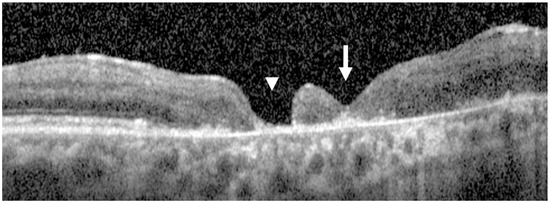

Expanded Case Study